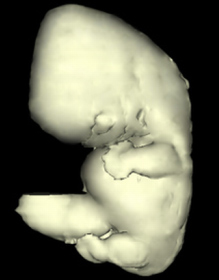

Carnegie Embryo #4430 | Location: 19-23

Source: The Virtual Human Embryo.